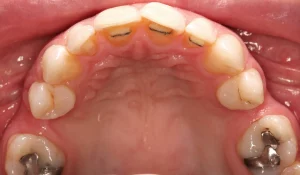

When this lady was younger, she had four teeth removed and then braces placed. However, the patient didn’t like her end smile; she felt it looked too narrow, so she sought more treatment.

At the beginning of treatment, the top gaps were too narrow to place the correct size of the premolar tooth. So braces were put on, and the gaps were opened up. When we achieved enough space, we could place the implants on either side of the top jaw. Porcelain crowns were placed on the implants. A while later, we added composite bonding on other teeth to further improve the patient’s bite, bringing additional comfort to her facial muscles and jaws.